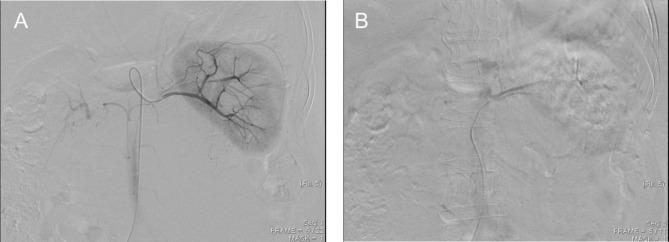

A 57-year-old woman with a negative family history of cancer presented at our Urology Department with a large left retroperitoneal tumor found by magnetic resonance imaging during the health exam. Physical examination showed a soft abdomen and no palpable mass or tenderness. Imaging studies showed that the tumor covered the entire left renal pedicle, but the left kidney, left adrenal gland, and pancreas appeared tumor free. Since the tumor tightly covered the entire renal pedicle, tumor excision with radical nephrectomy was advised. The patient underwent transarterial embolization of the left renal artery with 10 mg of Gelfoam pieces daily before surgical excision. Tumor excision and left radical nephrectomy were uneventful the day after embolization. Post-operatively, the patient recovered well and was discharged on day 10. The final histopathological analysis showed a round blue cell tumor consistent with an Ewing sarcoma, and the surgical margins were tumor free.